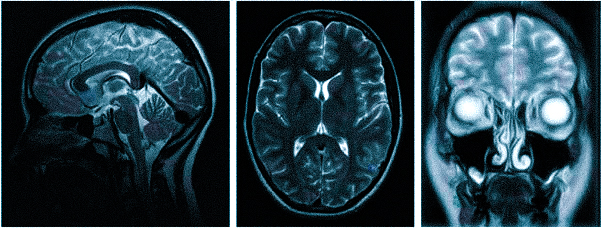

МРТ головного мозга. Обработка изображения в объеме и цвете.

Стандартным МРТ алгоритмом исследования при головных болях служит обследование 3 зон – МРТ головного мозга, МРТ сосудов головного мозга (МР-ангиография сосудов артериального круга мозга) и МРТ шейного отдела позвоночника. Неплохо дополнить этот набор исследований МР-ангиографией сосудов шеи. Каждый из перечисленных методов выполняет свои задачи. Очень редко назначают МР венографию сосудов головного мозга. Это связано с тем, что строение венозной системы очень индивидуально. Такие серьезные патологии вен, как тромбозы встречаются исключительно редко.

МРТ при головных болях (в трех проекциях): специальная программа выстраивает объемные изображения полученных срезов, что позволяет увидеть даже мельчайшие изменения и отдифференцировать патологию от нормы

Причин головной боли множество, и их не всегда возможно определить без помощи современных способов визуализации. Цефалгию вызывают: повышенное внутричерепное давление, сосудистые мальформации, опухолевые процессы, постравматические осложнения. Какую МРТ делать при головной боли или предпочтительней пройти КТ — зависит от предполагаемого характера патологии. Все методы являются взаимодополняющими, но что лучше в конкретном случае, выбирает врач с учетом жалоб, показаний и противопоказаний. МРТ и КТ с контрастным усилением позволяют получить сопоставимые по качеству снимки, но при этом используют разные принципы построения изображений. Чем раньше будет найдена причина и проведено адекватное лечение, тем больше шансов на полное выздоровление.

Выделяют несколько видов магнитно-резонансной томографии головы: нативную, усиленную контрастным препаратом и сканирование в ангиорежиме. К каждому исследованию есть свои показания, поэтому ответить на вопрос: “Какую МРТ делать при головной боли?” — не всегда возможно. Врач выбирает нужный тип диагностики, опираясь на клиническую картину. В оценке опухолевых новообразований и для определения стадийности (в том числе — метастатического распространения) используют МРТ с контрастированием. Введение препаратов на основе хелатов гадолиния позволяет рассмотреть даже небольшие опухоли в труднодоступных местах, поэтому магнитное сканирование с усилением с успехом применяют, если прочие способы визуализации показали неоднозначные результаты. При подозрении на сосудистое заболевание головного мозга оптимальным выбором будет проведение сканирования в ангиорежиме.